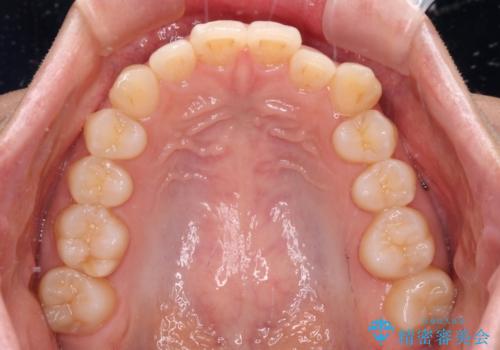

- 上下のクロスバイトと前歯のデコボコを気にして来院された患者様です。

インビザラインを用い、IPR(歯と歯の間を削る)と歯列全体を拡大させることで、歯並びを整えていくこととしました。

下の歯が隠れてしまうほどでしたが、深い咬み合わせも改善され、顎への負担も軽減されました。